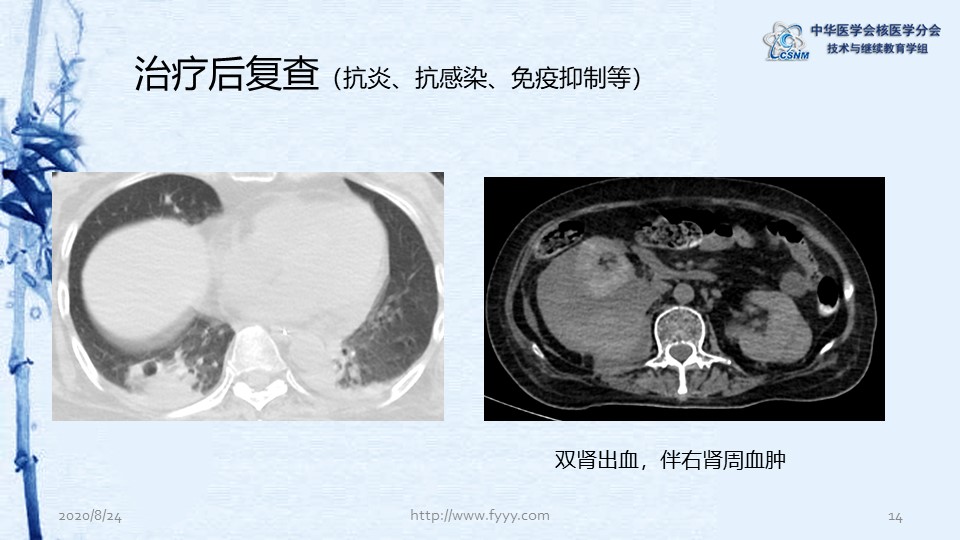

病例82:肉芽肿性血管炎PET-CT显像一例-【CSNM继教学组】郑山 福建医科大学附属第一医院